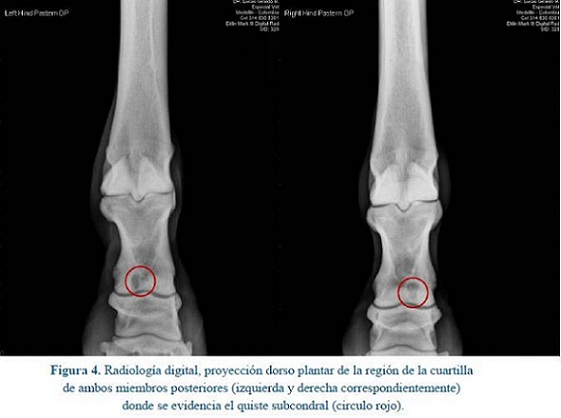

Se observa un área radiolúcida circunscrita a nivel del tercio distal de la primera falange, la cual se encuentra comunicada con la faceta articular de la articulación interfalángica proximal en ambos miembros posteriores. (Figura 4)

Posteriormente bajo anestesia genera, detallada a continuación, se realizó una evaluación ultrasonográfica detallada de la zona de la cuartilla a nivel de ambos miembros posteriores, observándose un área anecóica y falta de continuidad de la superficie ósea a nivel de la articulación interfalángica proximal en ambos miembros posteriores (Figura 5).